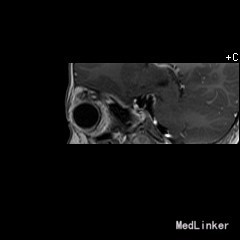

2岁9月患儿,因“左眼睑下垂1年余,头痛、呕吐8天”入院。家属1年前发现患儿左侧眼睑下垂,无法自行张开,一直未予特殊诊治。8天前患者哭闹频繁,诉头痛如爆炸样,剧烈难忍,并出现呕吐胃内容物数次,无伴抽搐、视力下降,无意识障碍。当地医院头颅MRI提示:左侧眼眶扩大,左侧眼球外上方泪腺区见一条状迂曲异常信号影,T1WI呈等信号,T2WI上病灶外缘呈高信号,内为等信号,增强扫描病灶中央呈条状明显强化影,边缘无明显强化,双侧大脑半球对称,灰白质对比正常,未见局灶性信号异常,左侧中颅窝前分蛛网膜下腔增宽,内为脑脊液信号;各脑室、脑池大小、形态均正常,中线结构居中,幕下小脑、脑干无异常,矢状面示垂体大小形态正常,未见局灶性信号异常;增强扫描未见明显异常强化。

患儿术后2周左眼睑下垂较术前好转。双侧瞳孔反射、眼球活动均无异常。 丛状神经纤维瘤主要发生于眼睑,在出生后或幼年时期即出现症状和体征。侵袭范围广泛,包括眼睑、眶内软组织、眶骨和邻近的脑、颞部等。眼部最早和最多见为上、下睑软性肥厚,皮下瘤组织增生,使上、下睑隆起。眼睑皮肤常有淡棕色色素斑,眼球向前突出和向下移位。眼球突出虽然很显著,但向眶内纳入并不困难。肿瘤组织可直接侵袭眶内各种结构,上睑提肌首先被波及,引起上睑下垂,上举不足或不能。MRI可准确显示病变的范围尤其显示病变与邻近结构的关系,也可清楚显示其他部位伴发的肿瘤,但难以清晰显示眶壁骨质改变。手术治疗是必要的,手术切除应注意以下问题:1.眼睑病变的切除;2.眶内病变的处理;3.提上睑肌的处理;4.眶骨缺失的处理。丛状型术前诊断容易,但治疗较为棘手,易复发。